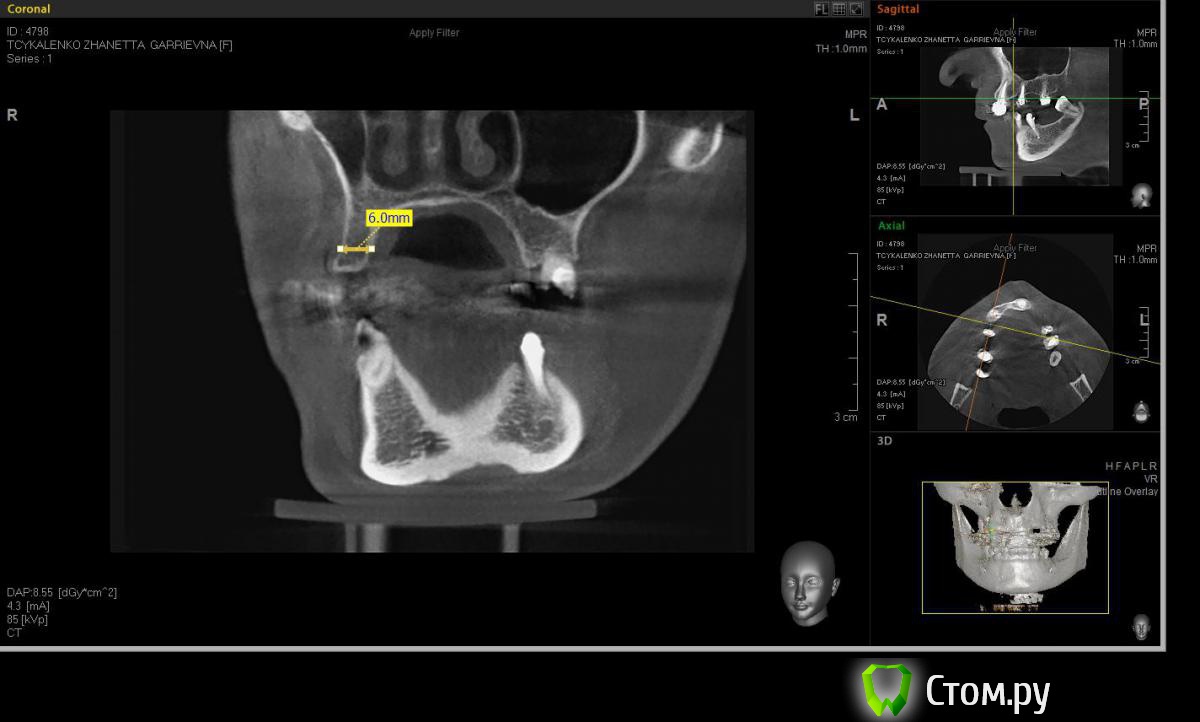

Евгений Ходыкин Опубликовано 20 мая, 2014 Автор Поделиться Опубликовано 20 мая, 2014 Замерил... Ссылка на комментарий

АнтонТЛТ Опубликовано 20 мая, 2014 Поделиться Опубликовано 20 мая, 2014 А теперь замерьте угол в районе 15 зуба через фиссуру Ссылка на комментарий

Евгений Ходыкин Опубликовано 20 мая, 2014 Автор Поделиться Опубликовано 20 мая, 2014 Ну как-то так. Сути не уловил) Свой зуб стоит совсем иначе, да и ширина гребня иная совсем... Ссылка на комментарий

АнтонТЛТ Опубликовано 20 мая, 2014 Поделиться Опубликовано 20 мая, 2014 Суть в том, что изначально не правильно угол замерили 1 Ссылка на комментарий

Евгений Ходыкин Опубликовано 20 мая, 2014 Автор Поделиться Опубликовано 20 мая, 2014 Суть в том, что изначально не правильно угол замерилиДак изначально я замерил строго по гребню, в условиях наибольшей ширины гребня, там угол под 30 и выходил. При ангуляции как у 1.5 у меня и получается дефицит кости, что примерно изобразил на схеме постановки имплантата. Поправьте, если не прав... Ссылка на комментарий

АнтонТЛТ Опубликовано 20 мая, 2014 Поделиться Опубликовано 20 мая, 2014 На кт зубе не в прикусе, но фиссурно-бугорковый контакт подразумевается. А там не глубокий прикус?Сделайте Wax-up и хир.шаблон с направлением сверления. А какой диаметр импланата планируется? Думаю нужно с нкр. Ссылка на комментарий